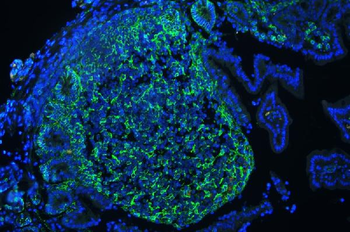

10 μg, 100 μg - Anti-S100 alpha 6/S100A6 Antibody [orb315184]

FC, ICC, IF, IHC, WB

Human, Mouse, Rat

Rabbit

Polyclonal

Unconjugated

10 μg, 100 μg - Anti-HSD11B2 Antibody [orb316541]